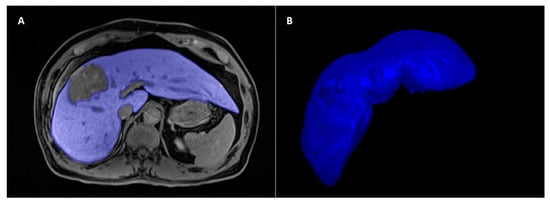

2.4. Liver Delineation and Radiomics Feature Extraction